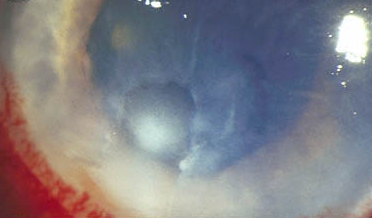

大疱性角膜病图谱

慢性角膜水肿导致上皮细胞容易脱落。